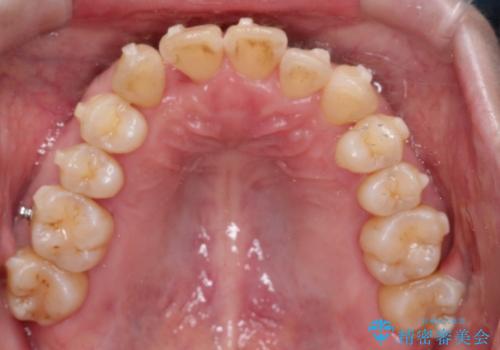

【インビザライン】ずれた前歯の噛み合わせをなおしたい

- 前歯の噛み合わせが悪いことを主訴に来院されました。

歯周病も併発していたため、歯牙への負担が少なくなるように治療計画をたて、インビザラインにて治療を完了しました。

矯正開始前に半年間、歯周治療を行ってからインビザラインを装着しています。